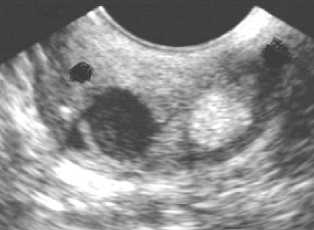

Ультразвуковое исследование с применением полостных датчиков - кисты шейки матки определяются как анэхогенные включения округлой или овоидной формы. Они могут быть как единичными, так и множественными. Чаще всего кистозные образования располагаются в эндоцервиксе, но встречаются и кисты стромы шейки матки. Внутренняя структура кист чаще однородная и анэхогенная, но иногда встречается неоднородное мелкодисперсное или гиперэхогенное содержимое с неровными контурами. Это связано с тем, что кисты возникают при нарушении оттока секрета желез, расположенных не только в слизистой оболочке цервикального канала, но и в мышечном слое. При цервикальном расположении кисты внутреннее содержимое кист не содержит сосудов. Усиление сосудистого рисунка в примыкающей строме не отмечается.

"Киста эндоцервикса на УЗИ".